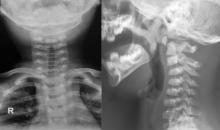

Espondilolisis cervical de C2 - Caso clínico y revisión bibliográfica

Se presenta un caso poco frecuente de espondilolisis cervical de C2, en un lactante de 1año y 7 meses de edad. Con el objetivo de mostrar las difcultades diagnósticas y terapéuticas, conociendo aquellos signos radiológicos que permiten identifcar esta infrecuente patología así como el algoritmo diagnóstico. Se optó por un tratamiento conservador con collarete, y se controló de forma regular obteniendo una muy buena evolución.